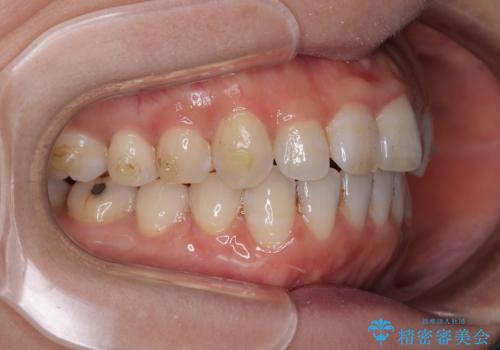

- 上下前歯が非接触となり、前方に突出していることを気にして来院された患者様です。

上下の前後差が大きいため、インビザライン単独での上顎歯列移動は困難と判断し、補助装置により上顎歯列を後方移動させ、その後インビザラインにて仕上げていくこととしました。

補助装置なしでも改善できる可能性はありましたが、補助装置で確実性を上げ、短期間できっちりと仕上げることができました。